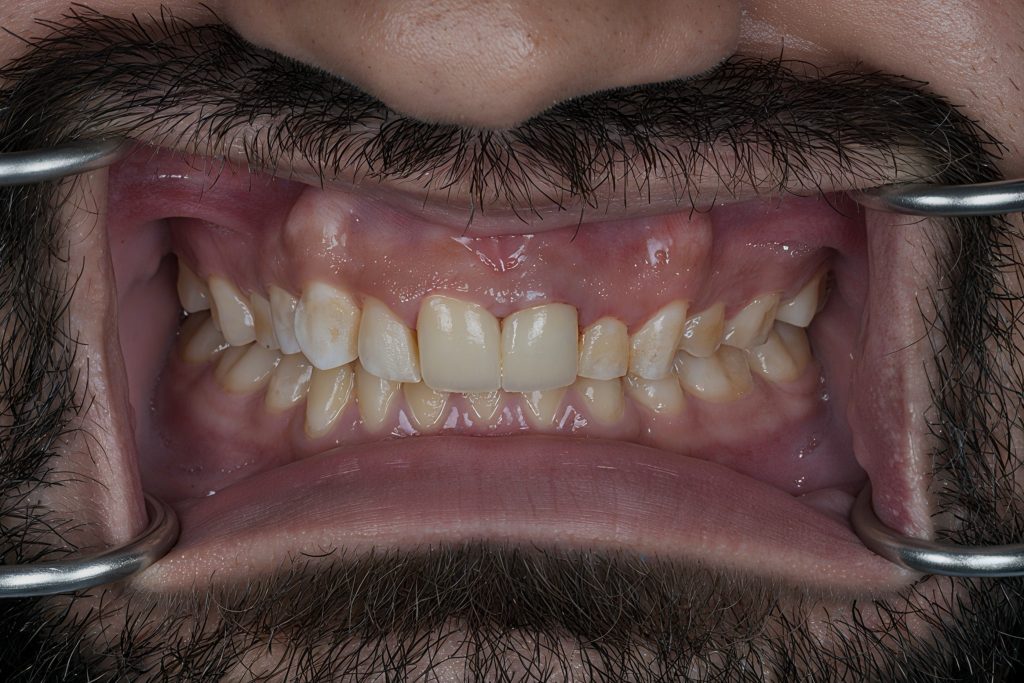

Pre-Operative Assessment

Clinical findings included:

- Irregular lengths and fractured enamel edges

- Poor axial inclination of centrals

- Previous composite restorations discolored and debonded

- Mild gingival inflammation

- Pulpal involvement confirmed radiographically

Primary goals: Restore function, protect remaining tooth structure, correct smile proportions, and achieve long-term stability.